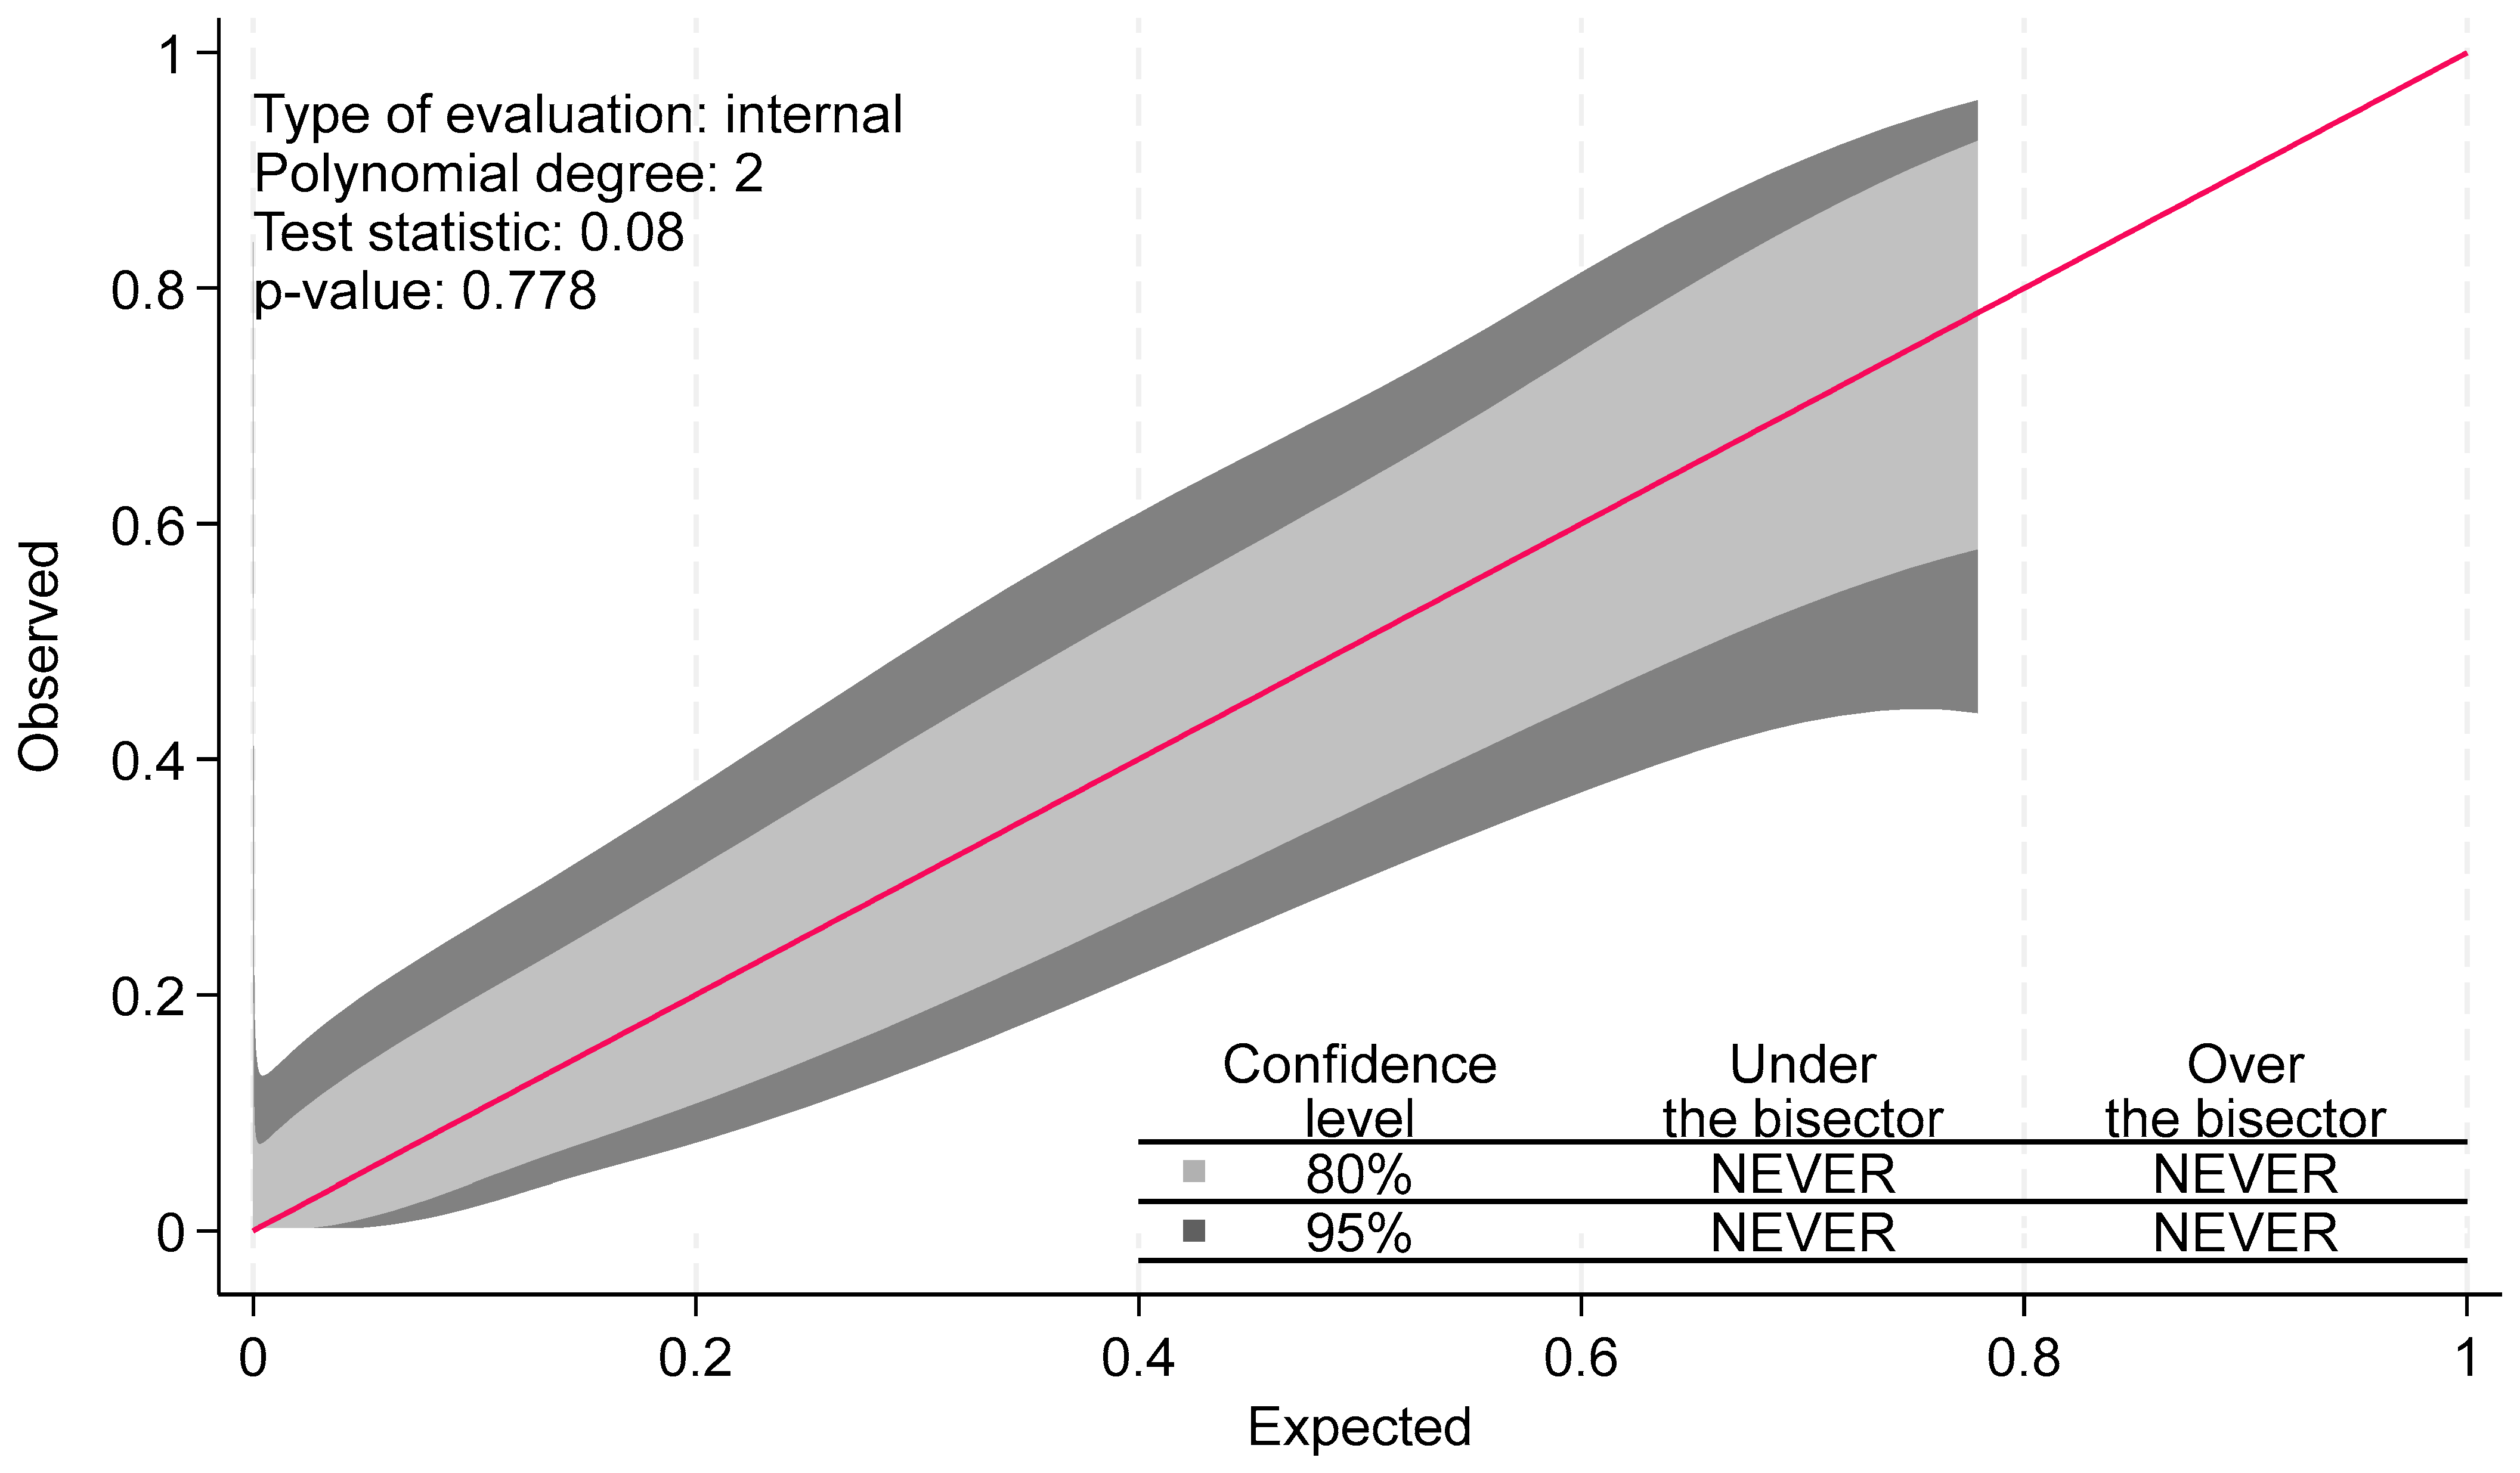

- Nattino, G.; Finazzi, S.; Bertolini, G. A new calibration test and a reappraisal of the calibration belt for the assessment of prediction models based on dichotomous outcomes. Stat. Med. 2014, 33, 2390–2407. [Google Scholar] [PubMed]

- Nattino, G.; Lemeshow, S.; Phillips, G.; Finazzi, S.; Bertolini, G. Assessing the calibration of dichotomous outcome models with the calibration belt. Stata J. 2017, 17, 1003–1014. [Google Scholar] [CrossRef]